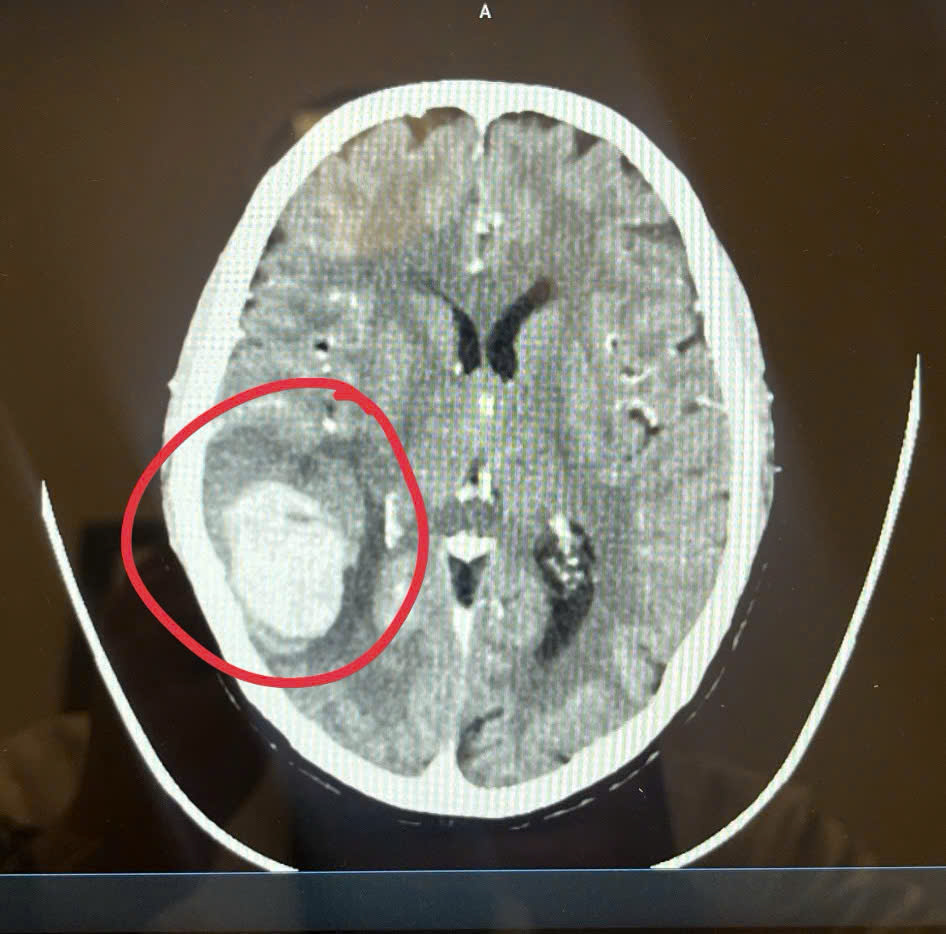

Khối xuất huyết não của bệnh nhân (ảnh: BSCC).

Theo bác sĩ Mạnh, khi khám thấy mặt bệnh nhân méo hẳn sang một bên, bác sĩ nghi ngờ bệnh nhân bị liệt dây thần kinh số 7 ngoại biên, chưa loại trừ đột quỵ. Bác sĩ đã cho bệnh nhân chụp CT, kết quả cho thấy não bệnh nhân bị xuất huyết, phù.